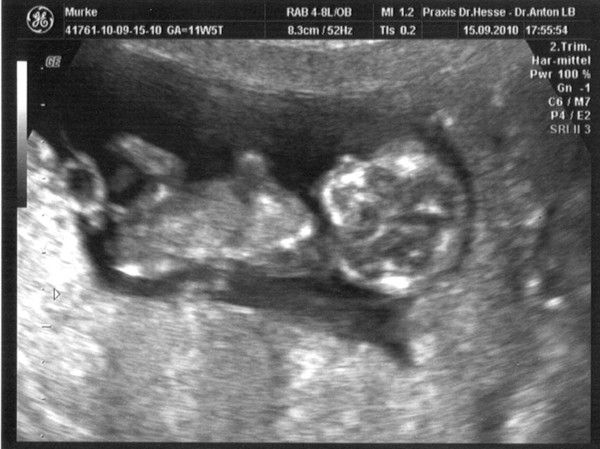

1.US_samulu_ET01042010

25.08.2010

zusehen ist schön der Embryo SSL 18mm; Markierung + ist Herzchen; rechts unten Nabelschnur und noch Dottersack

daraus ergibt sich eine Summe von ALLES OK in der 9.SSW (SSW8+5T)